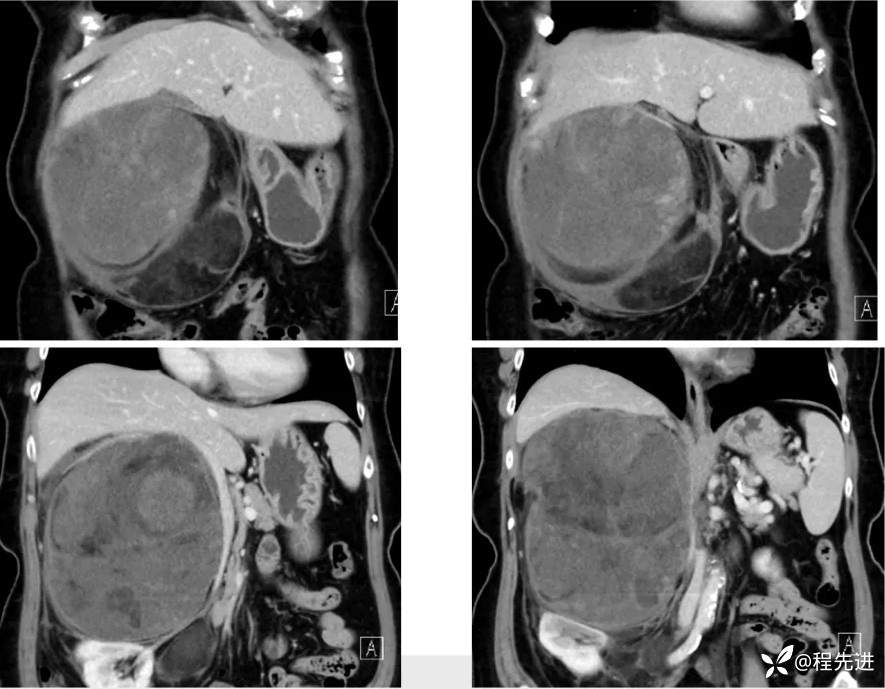

【主诉】:腹胀2月余,发现腹腔占位10天

【现病史及既往史】:患者2月余前出现腹胀,胃反酸,无寒战发热胸闷胸痛、恶心呕吐、腹痛腹泻等不适伴随症状。10天前患者自查发现腹腔占位

【检查】: